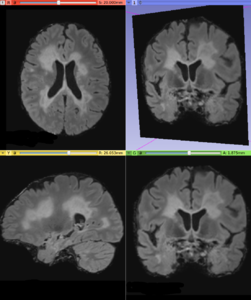

This module offers an implementation of a recent Multiple Sclerosis lesion segmentation approach based on a unsupervised method described by Cabezas et al. [1]. This module is intended to be used with FLAIR and T1 MRI volumes, which the MS lesions can be detected.

• Using T1 and FLAIR MRI volumes, it can be possible to detect abnormal voxel signal using a parametric strategy, which delineates white matter signals that does not belongs to the majority neighborhood pattern. More details can be found in the original paper [2]